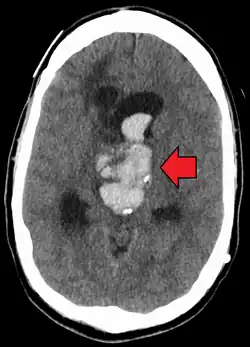

| Axiali CT scan of a spontaneous intracranial hemorrhage | |

A non-contrast CT scan (computed tomography) of the brain is commonly used as the initial imaging modality in suspected cases of intracranial hemorrhage. CT is preferred in emergency settings due to its speed, availability, and high sensitivity for detecting acute brain injuries, enabling rapid triage and surgical decision-making. Examples of brain diseases that require urgent intervention are: large-volume hemorrhage, brain herniation, and cerebral infarction. Additional advantages of CT imaging include its effectiveness in detecting bony fractures, vascular injuries, and cerebrospinal fluid (CSF) leaks.

A swirl sign on CT imaging— representing areas of low density with surrounding areas of high density— suggest active intracranial bleeding. The presence of this sign is associated with an increase in risk of death within one month and a poor functional prognosis at three months among survivors.[6]